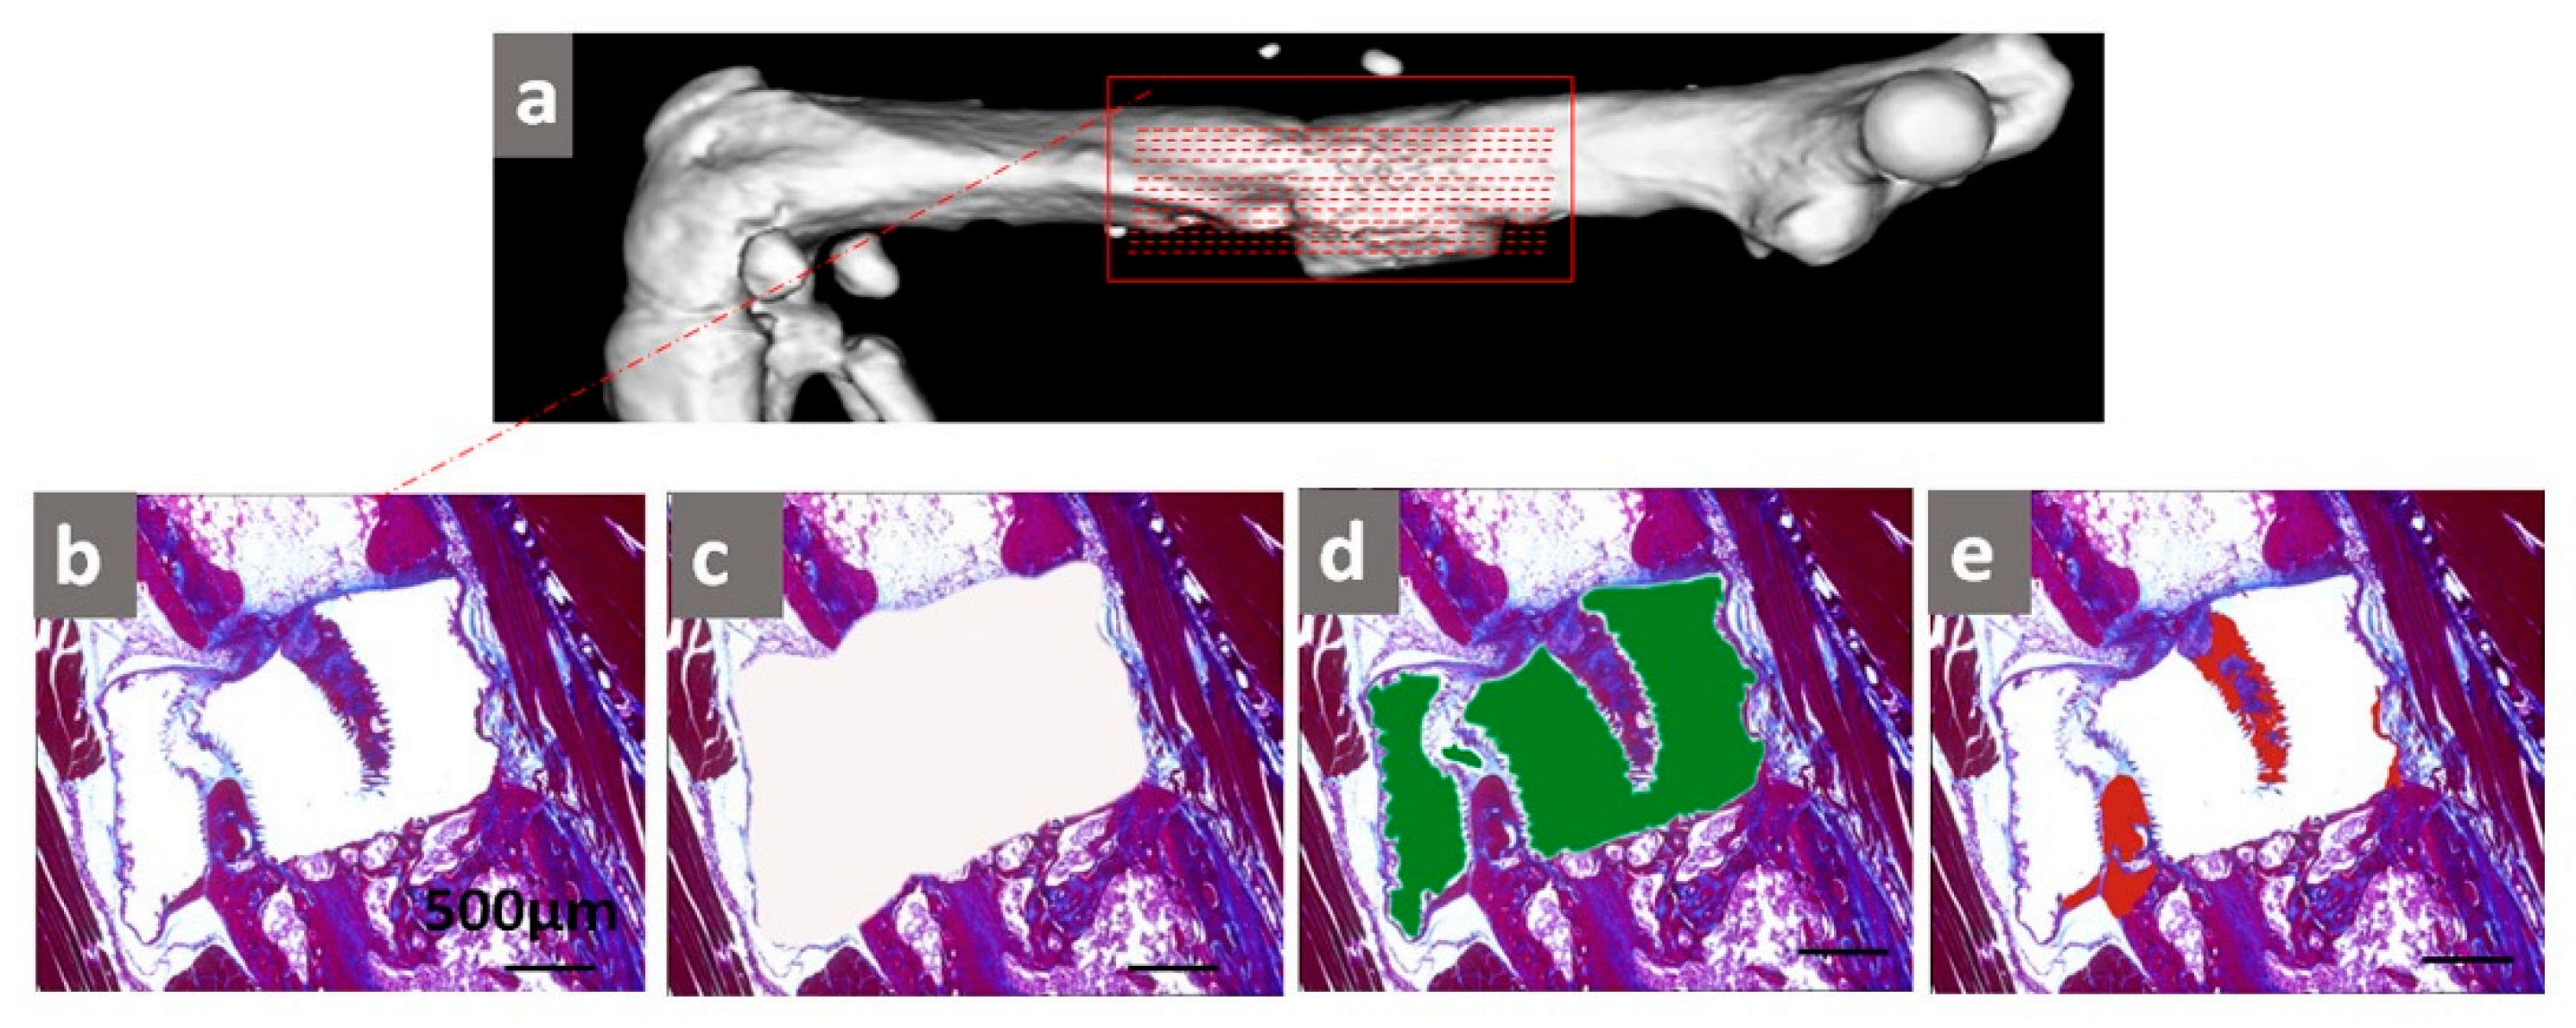

2.1. Longitudinal Monitoring of NF-κB Activity

2.3. Histological Analysis of Tissue Formation

4.5. Micro-CT Imaging

4.6. Histological Staining

4.7. AZAN Staining